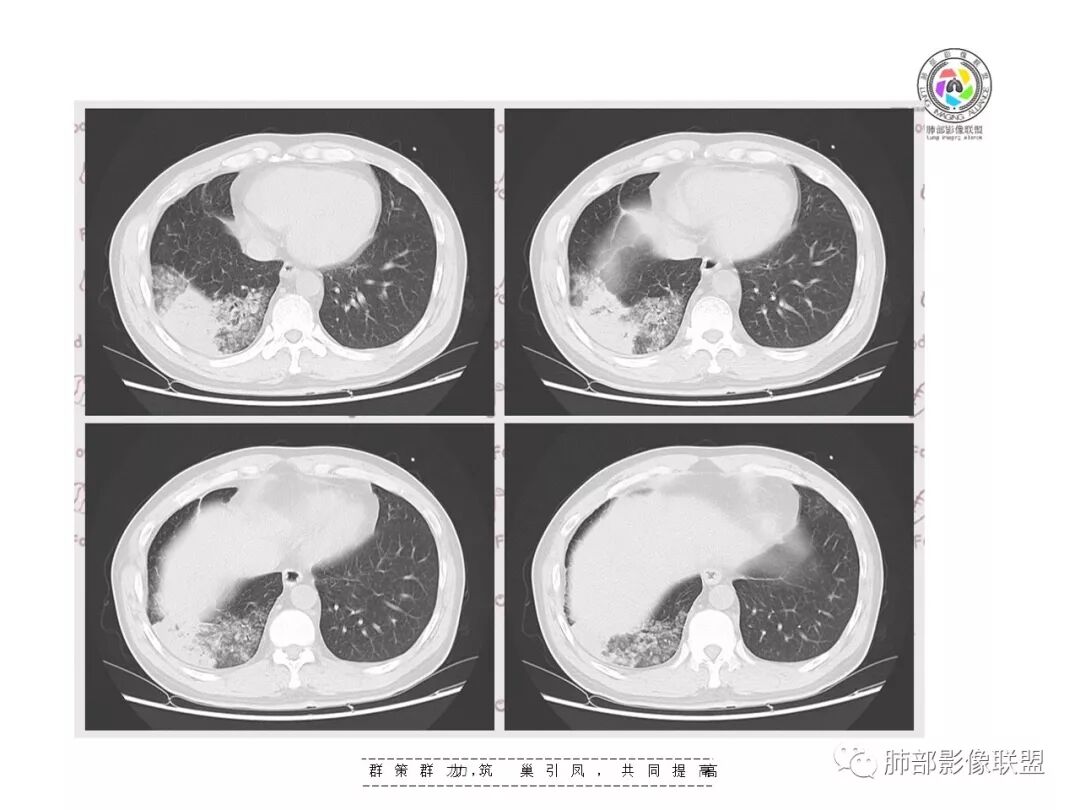

【影像资料】

张帅,首医附属潞河医院呼吸科:右肺下叶支气管开口明显狭窄,外基底段远端实变,内可见支气管征,周围可见弥漫结节样变,周围毛玻璃影,小叶间隔增厚,部分支气管壁不规则增厚,部分肺野可见小囊性变,壁部分增厚,右肺门明显增大,病灶与胸膜脂肪间隙增大,考虑恶性病变,腺癌。

王秀仙东宁市第二人民医院影像科:晨读:右肺下叶实变及磨玻璃影,边缘有收缩有膨隆,部分支气管进入扭曲扩张,磨玻璃影边缘清晰,实变影明显强化,内可见血管造影征,纵膈及肺门淋巴结肿大并强化,考虑粘液腺癌。

登封市三康医院(刘权威):右下肺肺不张,磨玻璃影,边缘清楚,空气支气管征,增强有强化,纵膈及右肺门淋巴结肿大并强化,考虑恶性肿瘤,粘液腺癌可能。

下叶外基底段为主实变,周围GGO

这个病灶很有特色

分布:沿支气管段、亚段朝外蔓延分布

实变+GOG

实变区边缘收缩,支气管走形自然

但是我们也可以看到实变区很多地方没看到支气管,也就是支气管在实变区分布不均匀,提示有些地方支气管腔内有物质填塞,显示不清

GGO边界大部分不清楚,内有树芽征,中央间质均匀增厚